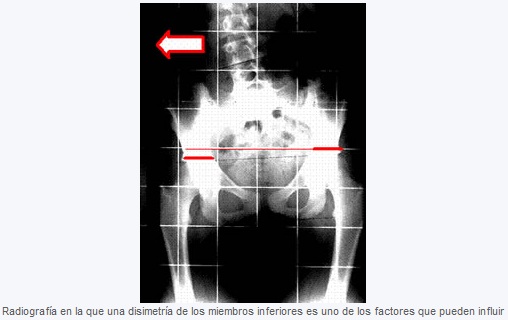

El tratamiento quiropráctico va dirigido a corregir los factores mecánicos en la columna que influyen en la progresión de la escoliosis, algunos tan simples como una dismetría de los miembros inferiores y otros más complejos como la manipulación específica de las vértebras.